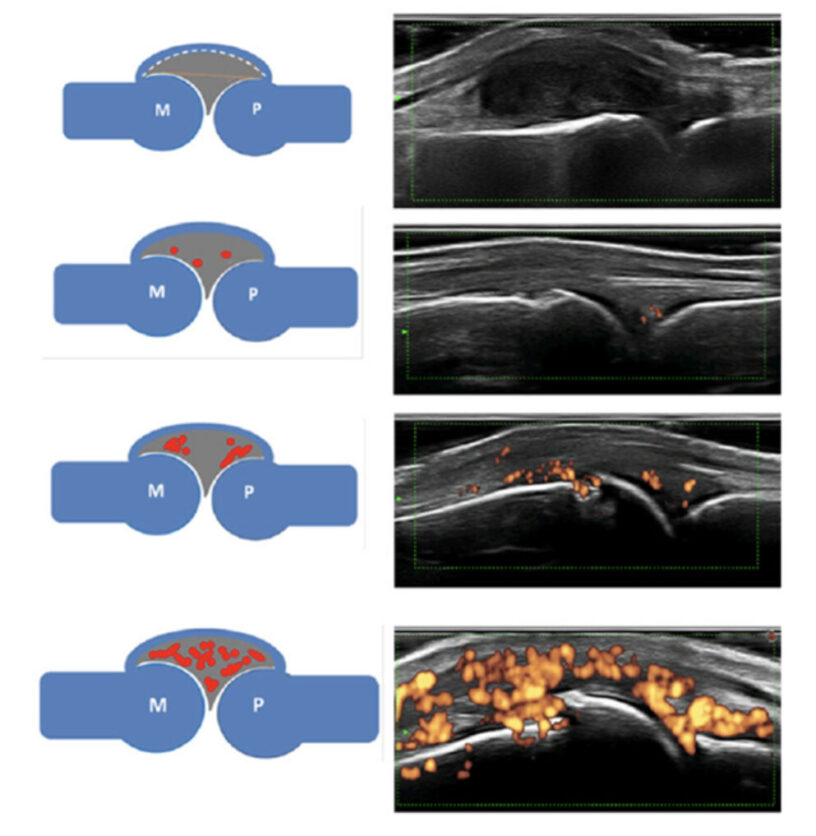

関節リウマチの進行機序

関節リウマチの画像検査

2.超音波検査

当然このような状態になってしまっては進行しているということです。リウマチは早期診断が大切な訳で近年では超音波検査やMRI検査で滑膜炎の状態を診ることが重要になります。

特に超音波検査は簡便鋭敏でパワードプラ法(血流信号)による炎症シグナルのグレード分類が2017年に提唱されるようになりました。治療効果を診る上でも超音波検査は有用で、数ヶ月に1回超音波検査を行い炎症状態が安定しているか診ることが重要です。

(2017年)

(2017年)